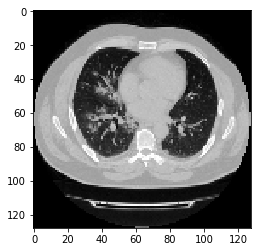

实例化数据集并显示一些图像。

import matplotlib.pyplot as plt

train_dataset = CTDataset(x_train,y_train)

images, labels = train_dataset[11]

image = images

print("Dimension of the CT scan is:", image.shape)

plt.imshow(np.squeeze(image[:, :, 30]), cmap="gray")

print("label is:",labels)

Dimension of the CT scan is: (128, 128, 64)

label is: 1

由于CT扫描有许多切片,因此让我们来看看切片的集合。